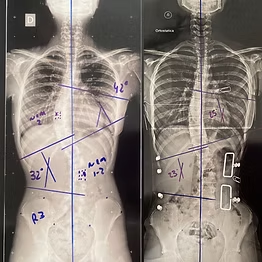

Avaliação inicial:

• 33 graus tóracolombar

Reavaliação 18 meses:

• 19 graus torácica

• 14 graus lombar

3 anos de Tratamento S4D, paciente de 14 anos. Realizou a sua avaliação na Escoliose Brasil Sede Salvador.